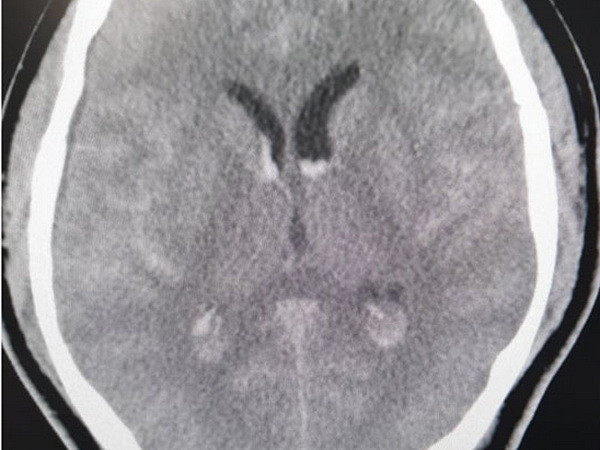

Cứu sống một bệnh nhân Hàn Quốc chảy máu dưới nhện nguy kịch ảnh 1Hình ảnh phim chụp xuất huyết dưới nhện lan tỏa - tụ máu não thất của bệnh nhân Hàn Quốc. (Nguồn: nhandan.com.vn)

Ngay khi tiếp nhận, các bác sỹ Trung tâm Đột quỵ đã nghi ngờ nguyên nhân chảy máu dưới nhện là do dị dạng mạch não. Bệnh nhân được đi chụp CTA - chụp mạch não phát hiện chảy máu dưới nhện lan tỏa - chảy máu não thất do vỡ phình lóc tách động mạch đốt sống phải đoạn V4.

Đây là một tổn thương có vị trí khó, phức tạp và tinh vi, thường cần một bác sỹ chẩn đoán hình ảnh chuyên sâu và nhiều kinh nghiệm mới chẩn đoán được.